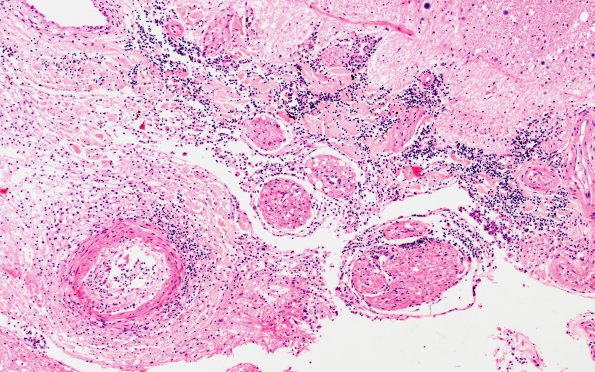

Washington University Experience | INFECTION | Bacteria | Meningitis | Meningitis, acute | 11D3 Meningitis (Case 5) Spinal cord WM 10X A

Closeup of the leptomeninges from 11D2. Note the infiltrate may involve larger vessels in the subarachnoid space (H&E)